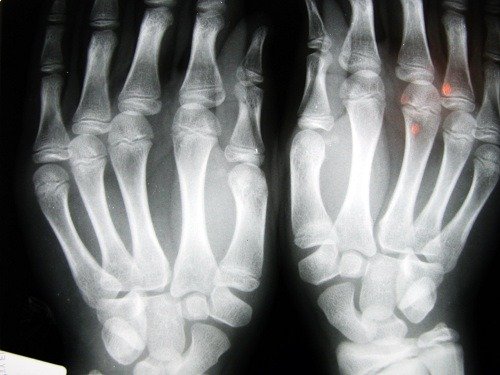

Osteoporoz kemik kitlesinin yoğunluğunda azalmaya neden olan bir kemik hastalığıdır. Bu hastalığın en karakteristik özelliği boşluklu kemiklerdir. Kemiklerin iç hücrelerinin boyutunu büyüterek daha narin bir hale gelirler ve daha kolay kırılırlar.